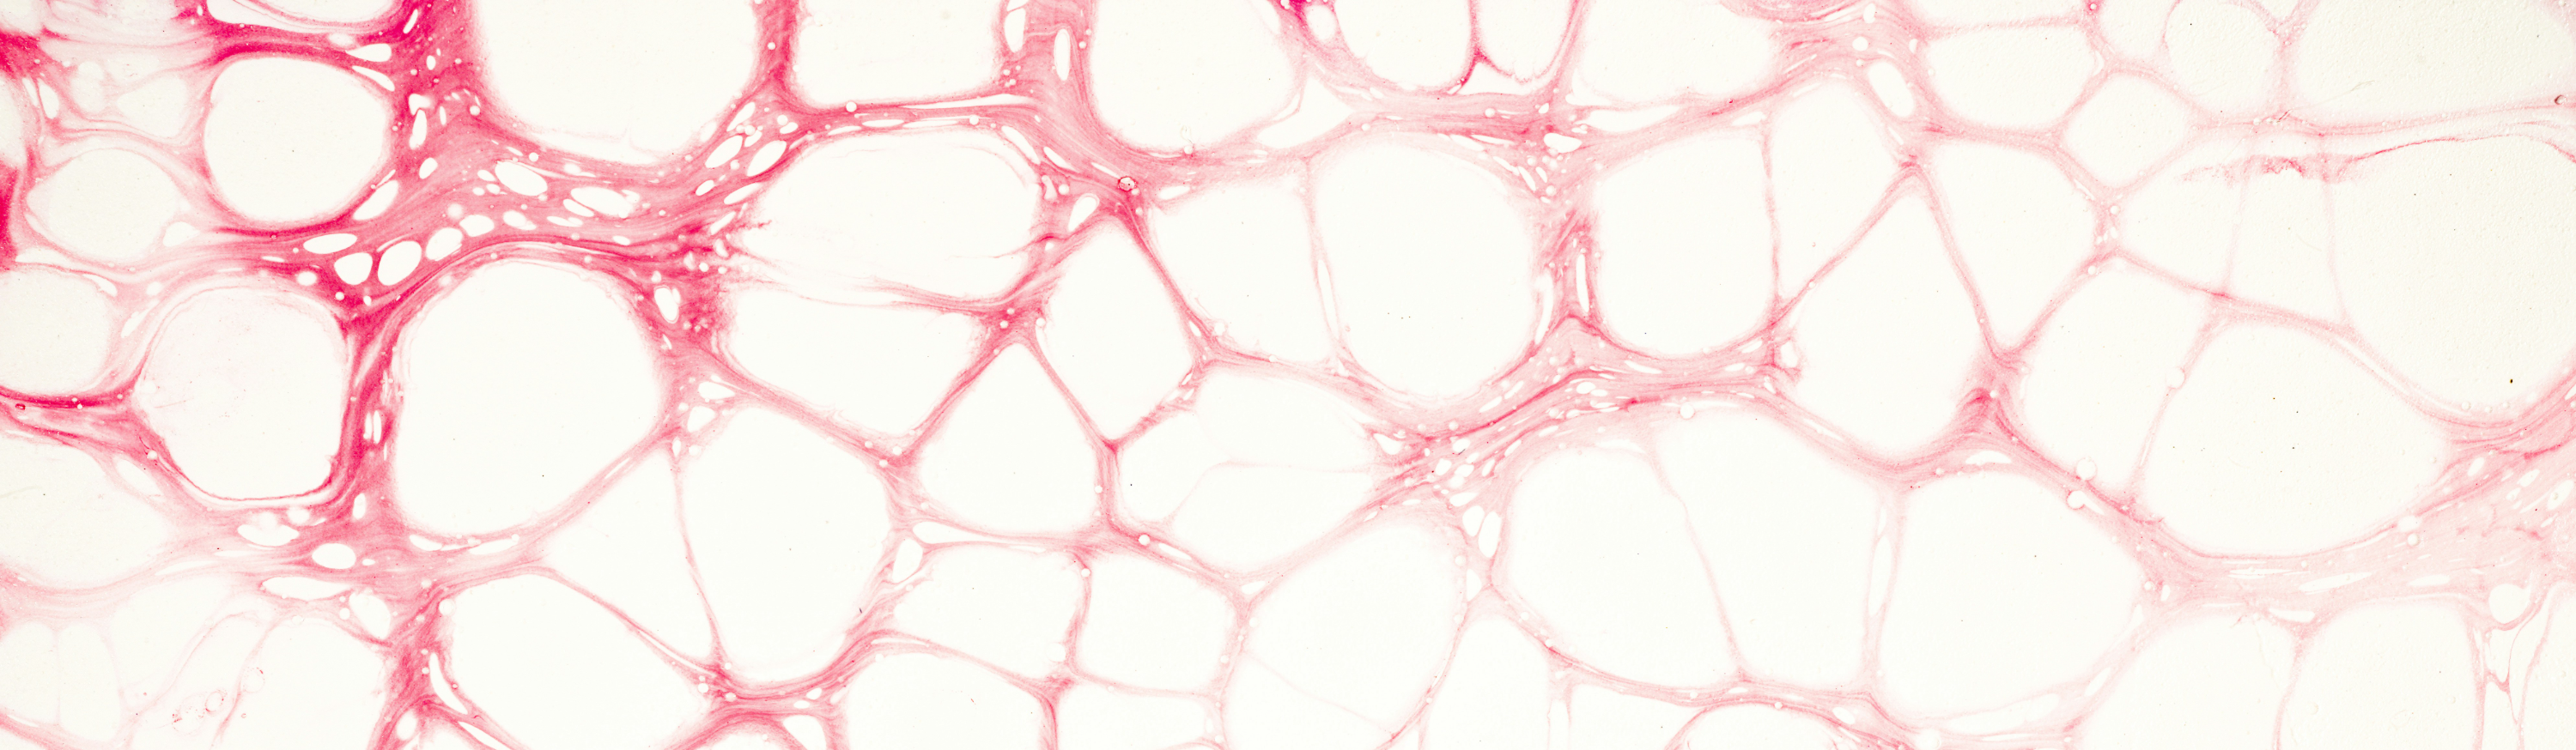

혈전증은 혈액 내의 응고 요인이 과도하게 활성화되어 혈관 내에서 혈전(혈관 내 혈액 응고물)이 형성되는 질환을 의미합니다. 혈전은 혈액이 응고되어 혈관을 막는데, 이는 혈액 순환을 방해하고, 혈액이 담겨있는 혈관 내에서 더 큰 문제를 유발할 수 있습니다.